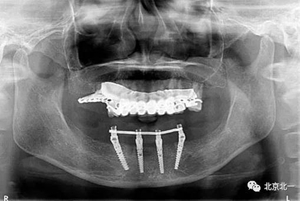

圖十五:術(shù)后即刻拍X片

圖二十一:半年后復(fù)查X片

圖二十二:2015年到2016年復(fù)查時(shí)X片 ,有圖有真相